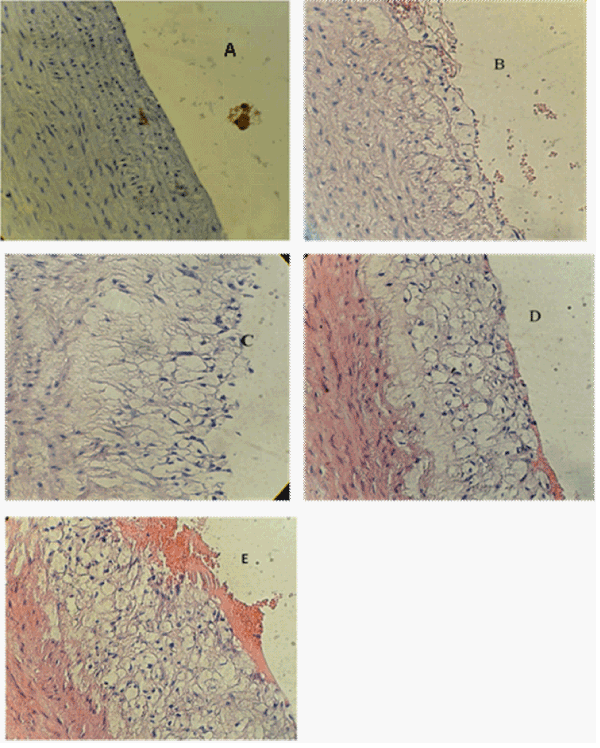

| Figure 2: A cross section of aortic arch from hypercholesterolemic rabbit represented atherosclerosis progression (x40). A: Normal arterial appearance, B: Initial atherosclerotic lesion characterized by lipid laden macrophage (foam cells), C: Intermediate atherosclerotic lesion characterized by extracellular lipid pool. D: Advance atherosclerotic lesion characterized by core of extracellular lipid and. E: Complicated atherosclerotic lesion characterized by haemorrhagic thrombus. |